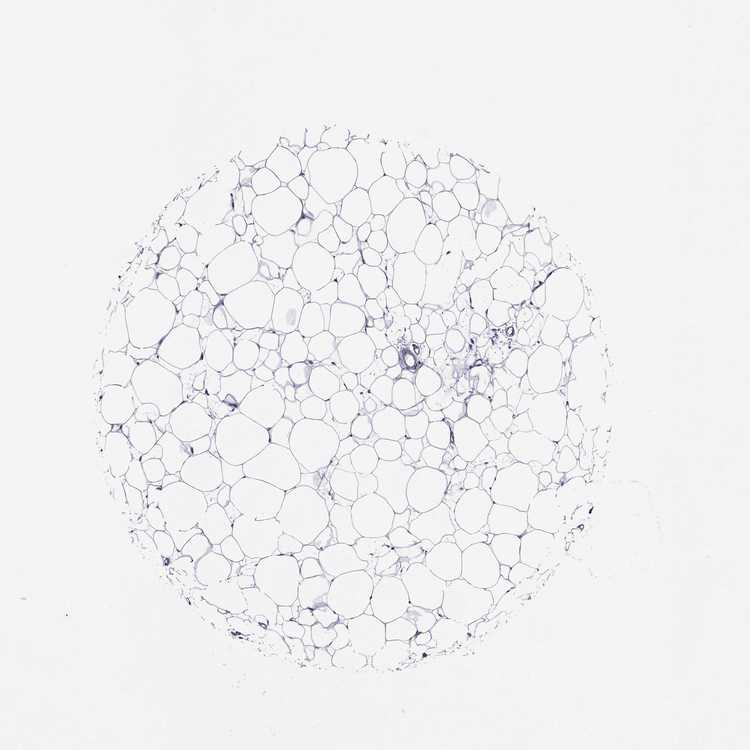

BREAST - Antibody stainingi

Antibody staining in the annotated cell types in the current human tissue is reported as not detected, low, medium, or high, based on conventional immunohistochemistry profiling in selected tissues. This score is based on the combination of the staining intensity and fraction of stained cells.

Each image is clickable and will lead to virtual microscopy that enables deeper exploration of all samples and also displays staining intensity scores, fraction scores and subcellular localization as well as patient and tissue information for each sample.

Antibody HPA019195

Adipocytes Not detected

Glandular cells Not detected

Myoepithelial cells Not detected